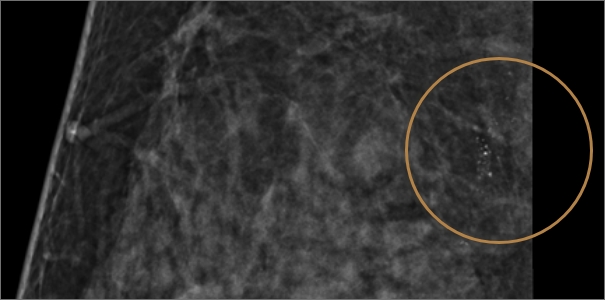

악성이 의심되는 미세석회화

조직검사로 암의 여부 판별

유방암으로 인해 발생한

악성 미세석회화로 의심되는 경우

맘모톰을 이용해 조직을 추출한 후

조직검사를 시행해 암의 여부를 판별합니다.

과거 여러 번 유방촬영을 진행하였지만 진단하기 어려운 치밀유방으로 인해 정상 판정을 받다가

진공흡인 보조장치(맘모톰)의 특수바늘을 통해 병변 확인해 보니

우측 유방 윗부분에 미세 석회가 발견되어조직 채취 후 암 진단 판정되어 치료 진행

치밀유방 여성, 우측 미세석회 발견

진공흡인 보조장치(맘모톰) 조직 채취 후

암 진단 판정